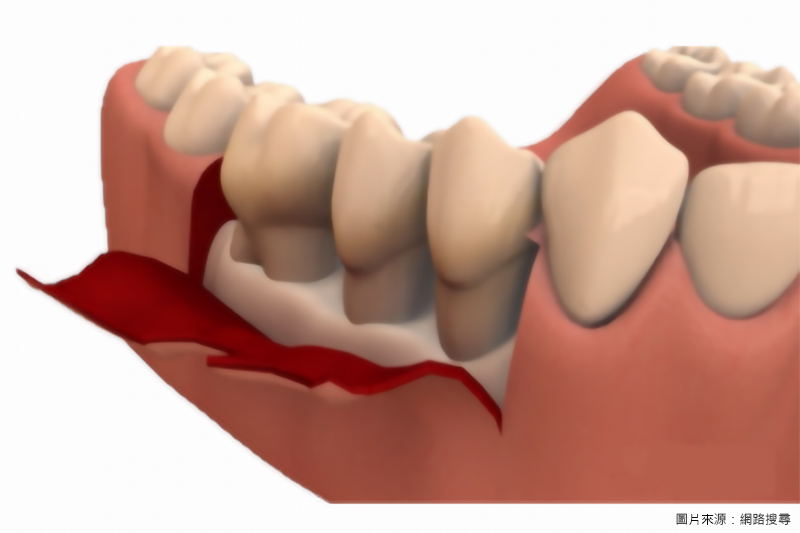

手術治療(翻瓣手術治療)

A. 經過牙周病基本治療後,通常有適當的觀察期(1~3月)。

B. 觀察期過後,若醫師評估仍有深的牙周囊袋,牙周發炎未能完全控制時,則需實施牙周病手術。

C. 一般牙周手術治療的目標在於徹底清除深度牙周囊袋內牙根上的結石以及發炎牙周組織。

D. 特殊牙周手術可配合各式牙周再生技術及材料,以促進牙周再生。

① 一般牙周翻瓣手術治療的目標在於徹底刮除深度牙周囊袋內牙根上的結石及發炎的牙周組織

② 特殊牙周手術可配合各式牙周再生技術及材料,以促進牙周再生